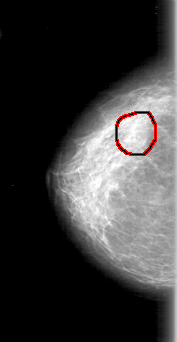

D_4066_1.RIGHT_MLO

RIGHT_MLO LINES 5206 PIXELS_PER_LINE 2671 BITS_PER_PIXEL 12 RESOLUTION 43.5 OVERLAY

FILE: D_4066_1.RIGHT_MLO.OVERLAY

TOTAL_ABNORMALITIES 1

ABNORMALITY 1

LESION_TYPE MASS SHAPE ROUND MARGINS OBSCURED

ASSESSMENT 0

SUBTLETY 2

PATHOLOGY BENIGN

TOTAL_OUTLINES 1

BOUNDARY